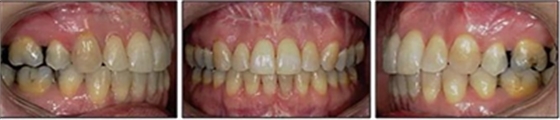

患者曾行正畸治療,現(xiàn)覺(jué)笑容不美觀前來(lái)就診?;颊哒嬗^及側(cè)貌示下頜發(fā)育不足,偏高角,唇閉合不全。上下頜中線(xiàn)齊。覆合、覆蓋4毫米。磨牙關(guān)系及尖牙關(guān)系II類(lèi)。上頜擁擠度4mm,下頜擁擠度6mm。4顆第一前磨牙在第一次正畸治療時(shí)已拔除。上下牙弓呈尖圓型,牙弓狹窄。

患者側(cè)貌改善,下唇唇肌緊張消失,上下唇可自然閉合。磨牙及尖牙關(guān)系糾正至I類(lèi),覆合覆蓋正常。上下頜弓型糾正至卵圓形,牙弓寬度增加。頭影測(cè)量分析示SNA角81.8°,ANB角3°。頭影測(cè)量重疊圖示下頜骨向后旋轉(zhuǎn),垂直面高度略有增加。